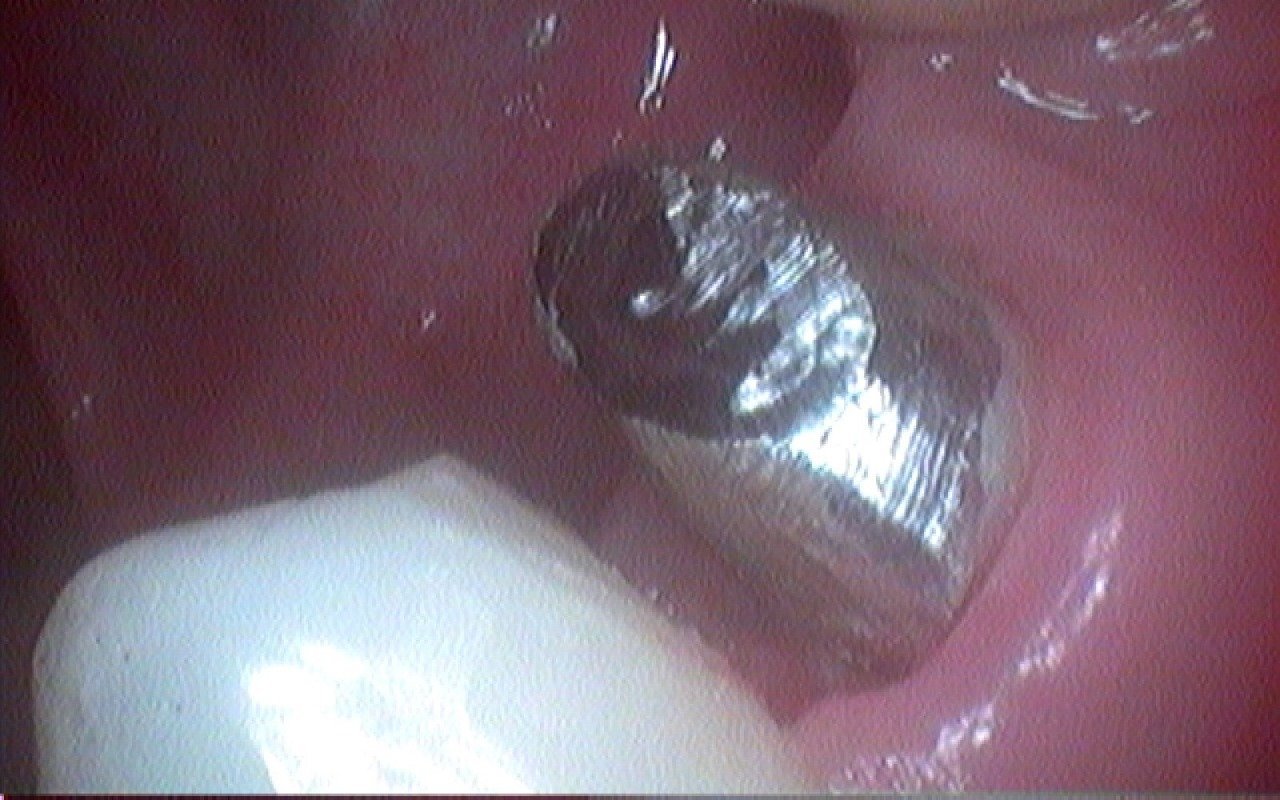

Фото работ врача Наиры Саргисовны Саргсян